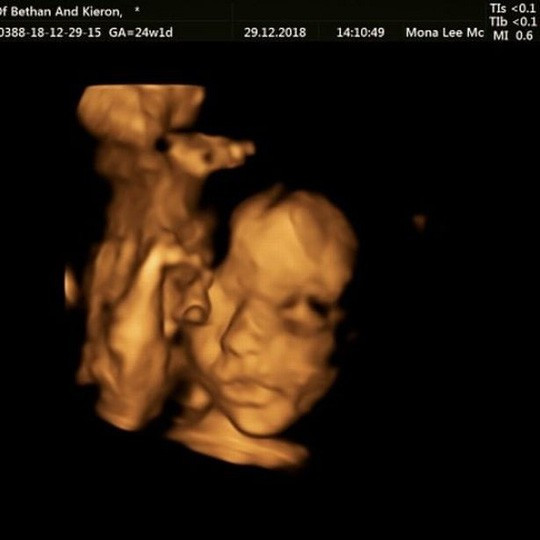

Kết quả siêu âm cho thấy thai nhi bị tật nứt đốt sống. Nếu không được chữa trị, nó có thể ảnh hưởng đến khả năng đi lại của đứa bé. Ảnh: Facebook.

Theo Mirror, các chuyên gia hàng đầu thế giới đến từ Bỉ và Anh đã tiến hành ca phẫu thuật khi thai nhi được 24 tuần tuổi, trong đó đóng vai trò chính là các chuyên gia phẫu thuật của Bệnh viện nhi Great Ormond Street - London.